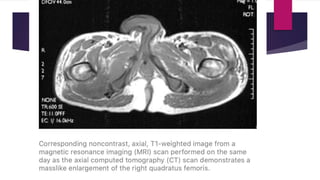

 MRI – isointense to hyperintense on T1 weighted images and

intermediate to high signal on T2 weighted images.

Stages of disease Early disease (inflammatory phase)  Pain and swelling (mimics infection or soft tissue aggressive tumor).  Radiograph – normal or soft tissue density seen.  USG – hypoechoic mass with a central reflective core is seen that may have a lamellar hyper reflectivity at the periphery of mass.  CT scan – enlarged muscle growth with normal attenuation.  MRI – isointense to hyperintense on T1 weighted images and intermediate to high signal on T2 weighted images.